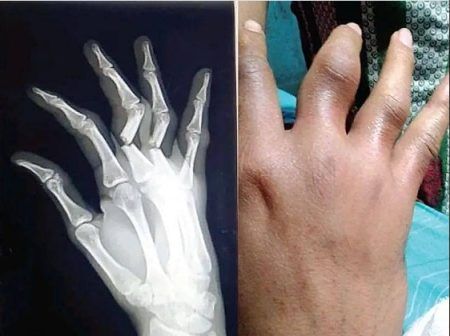

ಕಾರವಾರ: ಗೋವಾ ಪೊಲೀಸರ ಲಾಠಿ ಏಟಿಗೆ ಕಾರವಾರದ ಯುವಕನೊಬ್ಬನ ಕೈಬೆರಳುಗಳು ಮುರಿದಿರುವ ಘಟನೆ ತಡವಾಗಿ ಬೆಳಕಿಗೆ ಬಂದಿದೆ. ತಾಲೂಕಿನ ಚಿತ್ತಾಕುಲದ ನಿವಾಸಿ ಕಿಶನ್ ಶೆಟ್ಟಿ(22) ಎನ್ನುವ ಯುವಕ…